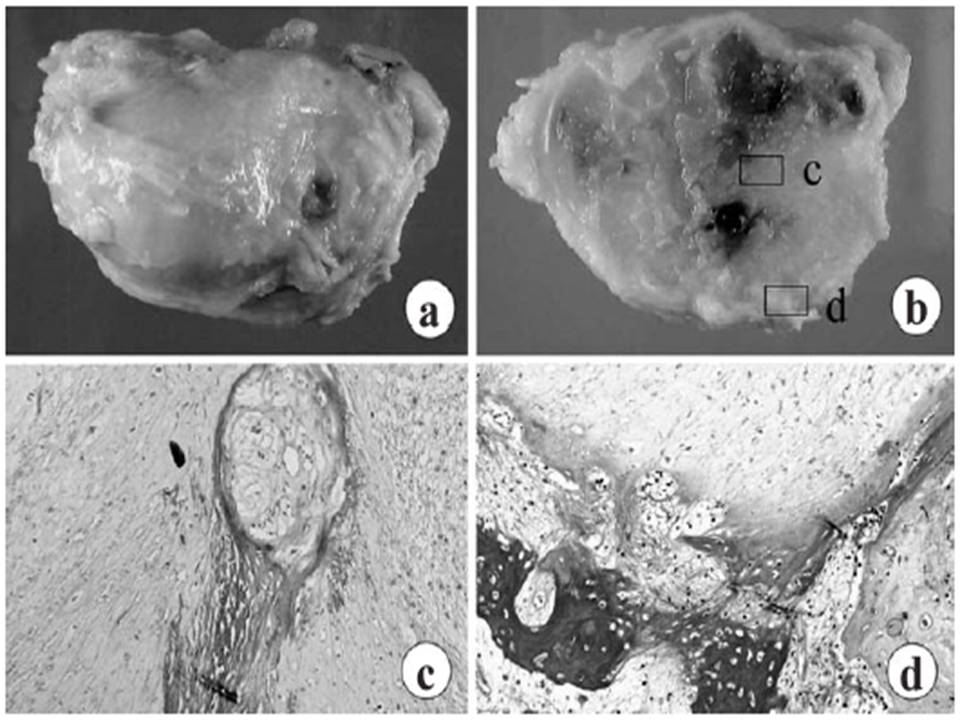

Gross and microscopic findings of the resected tumor. a) Gross appearance of marginally resected tumor. b) Cut surface. c) Microphotograph of the central portion of the tumor (area c in panel b). d) Peripheral region (area d in panel b).

H&E x 200

A histological study of the resected tumor showed necrosis at the tumor margin. |